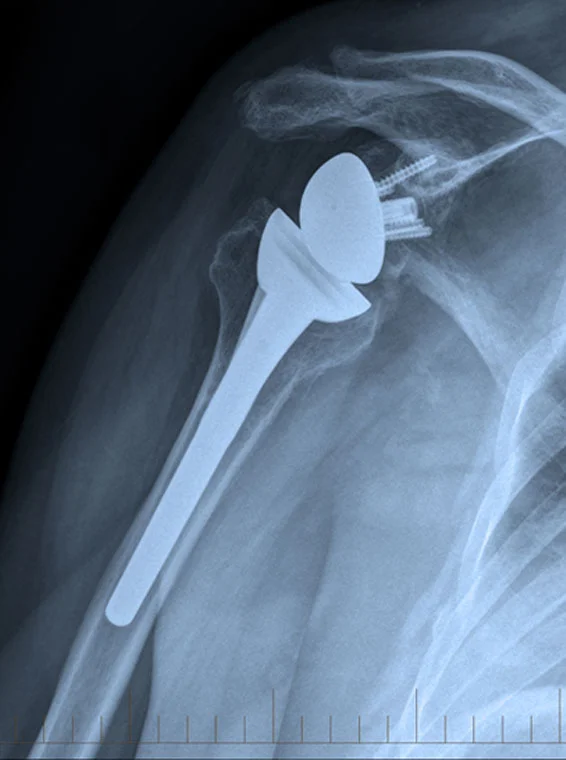

SURGICAL PROCEDURES & CONDITIONS OF THE SHOULDER

Shoulder Replacement Anatomic and Reverse